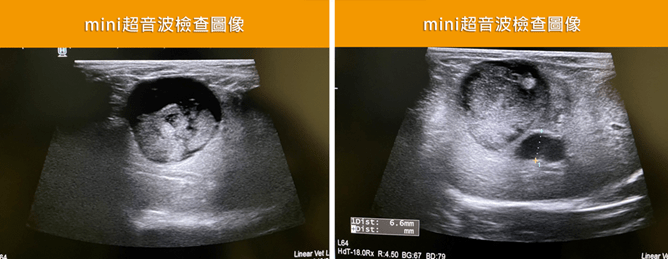

膽囊黏液囊腫原因未知,寵物會精神不振、嘔吐、食慾下降、活動力低落,或出現腹痛及黃疸。由於症狀並不明顯,只能用X光、腹腔超音波、血檢才能確認。血液檢查判別肝膽指數是否偏高,X光觀察肝腫大、及膽囊內容物礦物化的影響;腹腔超音波,更是最佳診斷工具,可以發現膽囊有回音性較高的物質,例如呈現典型星狀、或細條紋的膽汁影像,因此有『奇異果樣膽囊』的稱呼。

罹患『膽囊黏液囊腫』的貴賓犬!因行為異常而被帶到『啄木鳥動物醫院』就診。在血檢時發現肝膽指數偏高,做腹部超音波時,又發現肝腫大,膽囊黏性囊腫的情形,很可能是膽道阻塞引起的肝腫大及膽囊腫大。另外 Mini 的膽囊膽沙淤積阻塞現象,在超音波底下無所遁形,經過膽囊摘除手術,術後兩天就能正常吃喝了,但只要多拖延1~2天,一旦膽囊破裂就會有生命的危險。